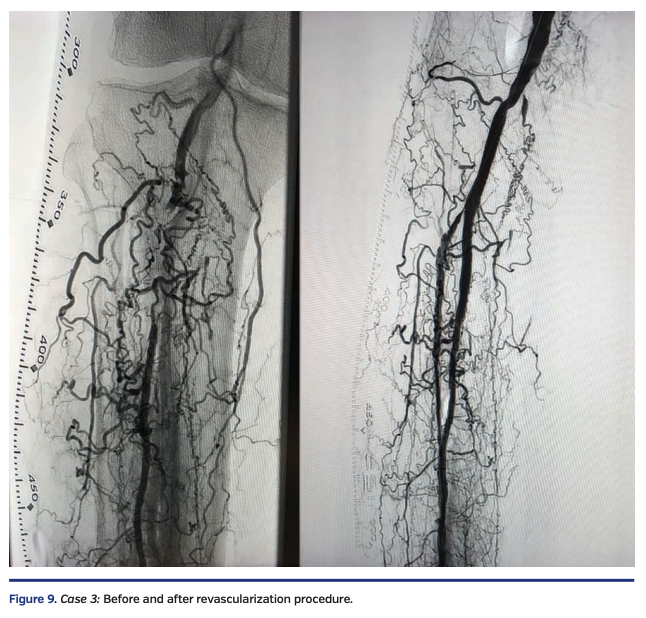

A white male in his early seventies with a history of type 2 diabetes presented with one year of claudication and a 2-month-old nonhealing ulcer at the tip of the right hallux with rest pain. Diagnostic angiography by a different physician revealed no evidence of right iliofemoral disease. The P3 segment of the right popliteal artery and the tibioperoneal trunk were occluded with recanalization of the mid peroneal artery via numerous collaterals (Figure 9, left).

A V-18 wire was advanced from the retrograde route and entered the subintimal space of the P3 segment of the popliteal artery. True lumen reentry was performed by advancing an Enteer wire with the aid of a 90 cm angled NaviCross catheter (Terumo) from the retrograde route. This wire was then exchanged out for a Fielder FC wire, followed by directional atherectomy of the right peroneal artery, right tibioperoneal trunk, and right popliteal artery, with a HawkOne M catheter advanced from the Prelude Ideal sheath, followed by balloon angioplasty with a 3.0 x 80 mm NanoCross balloon (Medtronic) and a 4.0 x 80 mm IN.PACT Admiral drug-coated balloon in the popliteal. Residual popliteal artery disease was treated with a 6 x 80 mm EverFlex self-expanding stent (Medtronic), post dilated in the proximal segment with a 6 x 40 mm and a 4 x 40 mm EverCross balloon (Medtronic) in the distal segment. To maximize blood flow and aid healing, right dorsalis pedis artery access was obtained with ultrasound and a 4 Fr merit Prelude Ideal sheath was advanced into the right distal anterior tibial artery. A knuckled Fielder FC wire was advanced into the true lumen of the right anterior tibial artery and right popliteal artery, followed by balloon angioplasty with a long 3.5 mm NanoCross balloon (Medtronic). Final angiography showed a widely patent right popliteal artery, tibioperoneal trunk, and peroneal artery (Figure 9, right). The ostium of the right anterior tibial artery was pinched, but there was normal flow in the right anterior tibial artery. There was complete resolution of the rest pain by the end of the procedure.